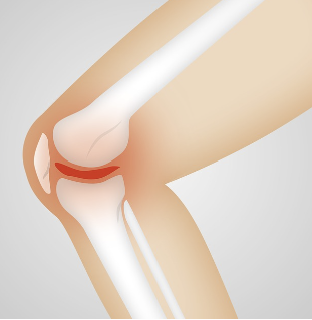

무릎 류마티스 관절염이란 무릎 관절에 염증이 생겨 통증, 부기, 뻣뻣함, 그리고 관절의 기능 상실을 일으키는 만성 염증성 질환입니다. 이 질환은 면역체계가 건강한 관절 조직을 공격하기 때문에 자가면역질환으로 분류됩니다